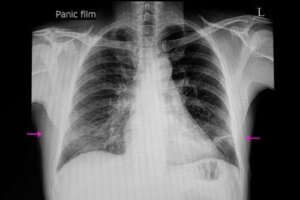

Om atelectase te diagnosticeren, is een gedegen klinische verkenning en een röntgenfoto meestal voldoende. Toch kunnen artsen een reeks technieken gebruiken om de diagnose te bevestigen of de ernst ervan te bepalen.

Deze technieken omvatten een CT-scan (computertomografie), bronchoscopie, echografie en oximetrie (Spaanse link). In feite maakt bronchoscopie het mogelijk om obstructies te observeren en zelfs blokkades op te heffen.